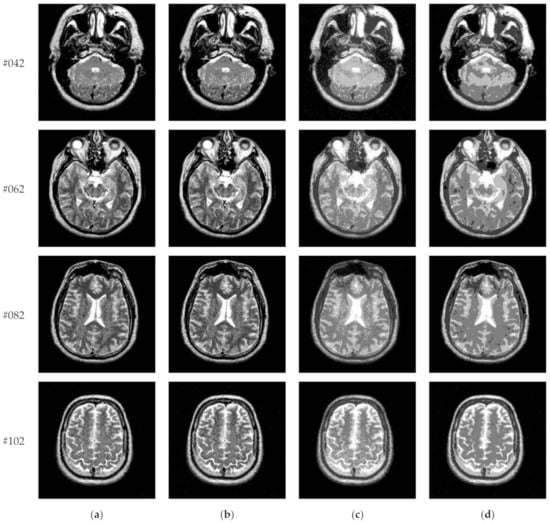

Figure 14 displays the segmentation results of images containing noise with a single level of thresholding K = 1. It can be observed that segmentation results achieved by HL-IIMT and Proposed are distinctly better than those of Otsu and IIMT, which have many isolated points. Figure 15 depicts segmentation results obtained by different algorithms with multilevel thresholding K = 4. Obviously, segmentation results of Otsu, IIMT, and HL-IIMT are seriously affected by noise, and most regions are blurred. However, the results of Proposed are better, and they have less noise and clearer edges.

Figure 14.

Segmentation results obtained by different segmentation algorithms for images containing noise (K = 1): (a) Otsu, (b) IIMT, (c) HL-IIMT, (d) Proposed.

Figure 15.

Segmentation results obtained by different segmentation algorithms for images containing noise (K = 4): (a) Otsu, (b) IIMT, (c) HL-IIMT, (d) Proposed.

A comparison of the evaluation results for different segmentation algorithms on images containing noise with K = 1, 4 is shown in Table 3, and corresponding comparison charts are given in Figure 16. In Table 3, the best results are marked in bold. It can be noted that Proposed consistently has the highest U values. For images containing noise, both the IIMT-based algorithms (HL-IIMT and Proposed) are superior to the original Otsu method in single threshold segmentation; furthermore, Proposed can achieve satisfactory results in multilevel threshold segmentation compared to the other three algorithms (IIMT, HL-IIMT, and Otsu).